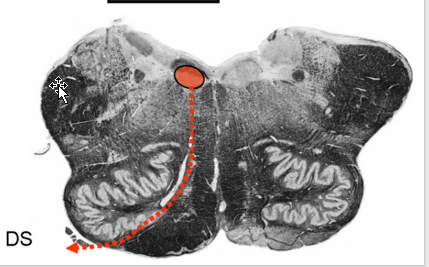

Describe the Pyramidal (Motor) Decussation

Location

Fiber Destiy

Somatotopy of Decussation

Location:

ventral surface of the medulla; disruption of the anterior median fissure

Fibers Destiny Here:

80-90 percent of corticospinal tract fibers decussates (L CST)

8% descend ipsilaterally → anterior funiculus → decussate segmentally (Anterior CST)

2% descend ipsilaterally to contribute to the lateral corticospinal tract (tract of Barnes)

Somatotopy of Decussation:

Upper Extremity fibers: Rostrally

Lower Extremity fibers: Caudally

THUS: iscrete lesions in the pyramidal decussation may produce different and somewhat unusual patterns of weakness.